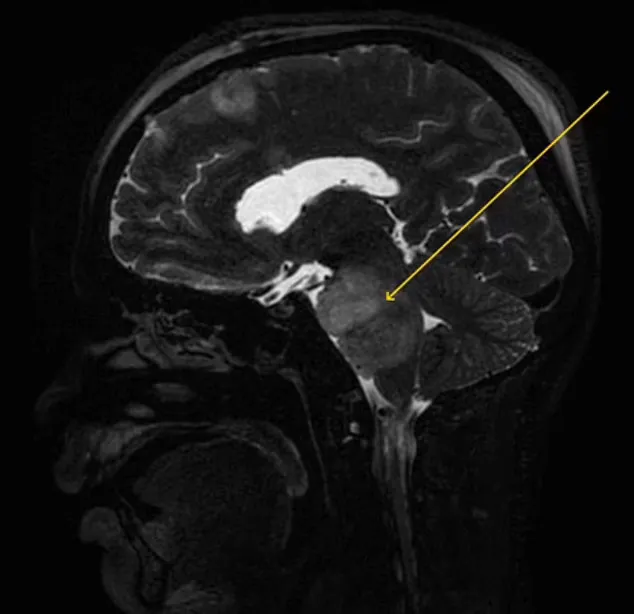

Результаты показали странную область в головном мозге мужчины, поэтому врачи отправили его на дополнительное МРТ-сканирование, чтобы определить происхождение неизвестного пятна.

Оказалось, что подсвеченная область в головном мозге является понтийской глиомой — это злокачественная опухоль, расположенная на стволе мозга. Из-за опасного расположения этот тип новообразования невозможно удалить хирургическим путем.